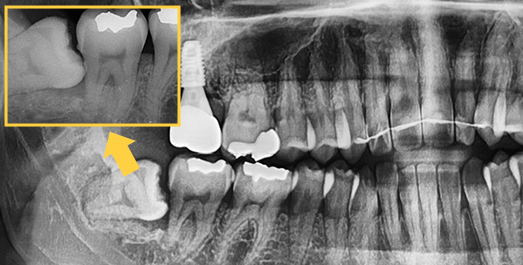

Even advanced cases

can be extracted.

With extensive experience in numerous advanced cases and a wide range of wisdom tooth extractions, you no longer need to go to a university hospital.

• BEFORE

• AFTER

Treatment Date : 2024.09.04

Treatment Date : 2023.12.22

Treatment Date : 2024.05.28